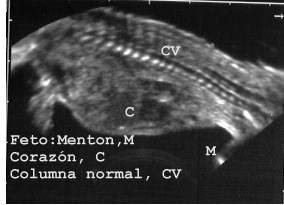

En los niños e individuos adultos delgados las posibles lesiones en columna vertebral son muy fáciles y seguras de diagnosticar por ecopsia (Fig 71)

71FETOCV.JPG (23851 bytes)

Fig 71